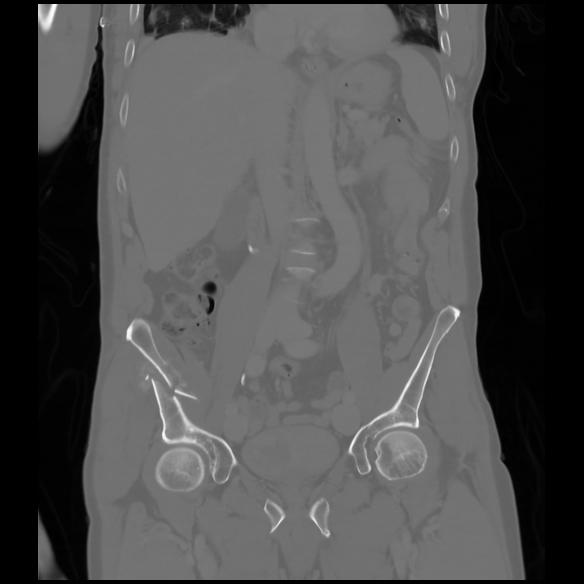

6 CUERPO,CE,Coronal,3.000,CUERPO,Coronal,